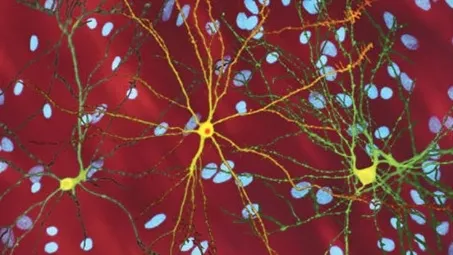

Болезнь Хантингтона вызвана избыточными повторами ДНК в гене хантингтин, что приводит к производству дефектного белка, медленно отравляющего мозг. Симптомы обычно появляются в возрасте 35-55 лет и включают нарушения координации, непроизвольные движения, резкие перепады настроения и постепенную потерю памяти. До сих пор не существовало терапий, воздействующих на причину болезни.

Новая генная терапия использует безвредный вирус для доставки в пораженные участки мозга инструкций по производству микроРНК. Эта молекула блокирует работу дефектного гена, останавливая выработку токсичного белка. После однократного введения клетки продолжают производить терапевтическую микроРНК постоянно. Процедура требует сложной нейрохирургической операции с применением МРТ-навигации для точного введения препарата в стриатум — область мозга, наиболее пораженную при болезни Хантингтона.